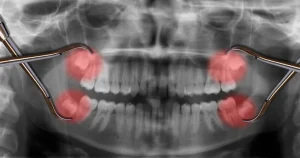

親知らずの生える本数は人によって異なり、4本すべての親知らずが生える方もいれば、1本も生えない方もいます。

そして、4本すべての親知らずが生えている方の中には、一度に4本の親知らず抜歯を希望する方も少なくありません。

今回は、親知らずを4本同時に抜けるケースと抜けないケース、同時に抜歯する場合のメリットやデメリットを解説します。